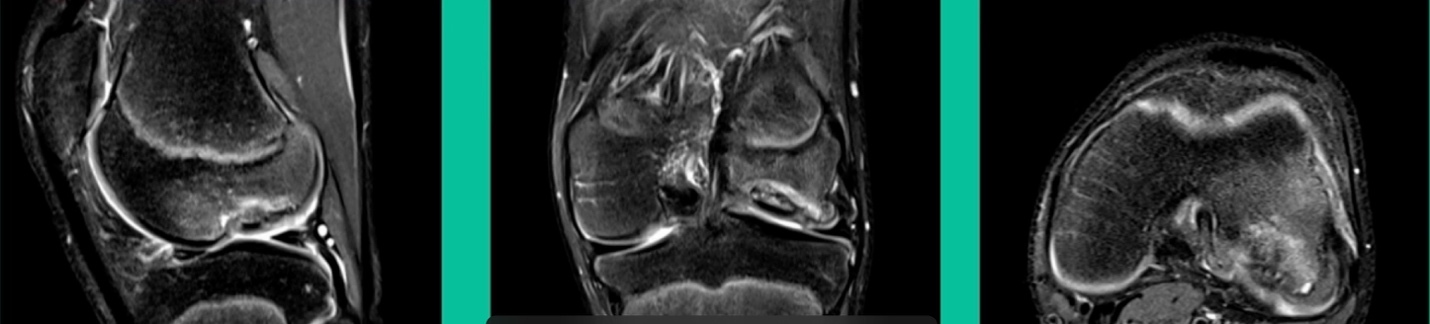

Now a couple of quick cases. This is juvenile OCD. This is the first series of three or four, just juveniles. 14-year-old, intermittent knee pain, lateral femoral condyle OCD (Figure 1).

This is an 11-year-old. Left knee lateral knee pain. Effusions, the same type of classic findings (Figure 3)

This is another one. 17-year-old basketball player (Figure 5).

Another case example. 14-year-old male tennis player, 10 months of knee pain (Figure 7A).

This is a Trochlear defect (Figure 7B).

Now, we’ll shift to the adult. This is a 27-year-old. Right knee swelling, activity-related, and classic failed nonsurgical treatment on the lateral side of the knee.

This is an 18-year-old with a lateral femoral condyle OCD: